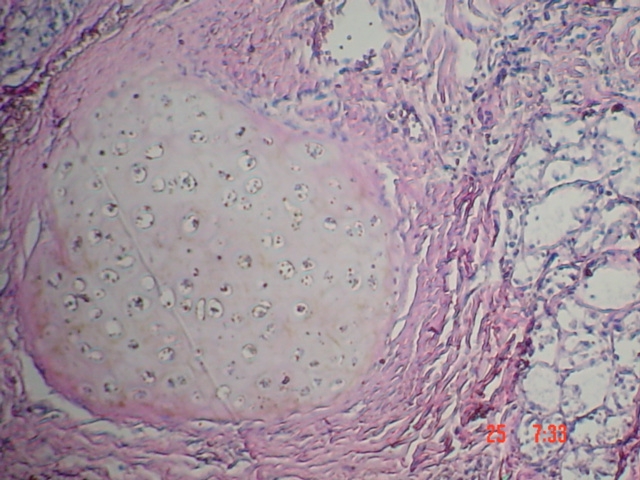

- <div style=fiogf49gjkf0d Fig. 6-7 Se observa hacia uno de los extremos epitelio cilíndrico ciliado de tipo respiratorio, subyacente al cual apreciamos tejido conectivo vascularizado con infiltrado inflamatorio y parénquima pulmonar. H-E 100X">

Fig. 6-7 Se observa hacia uno de los extremos epitelio cilíndrico ciliado de tipo respiratorio, subyacente al cual apreciamos tejido conectivo vascularizado con infiltrado inflamatorio y parénquima pulmonar. H-E 100X